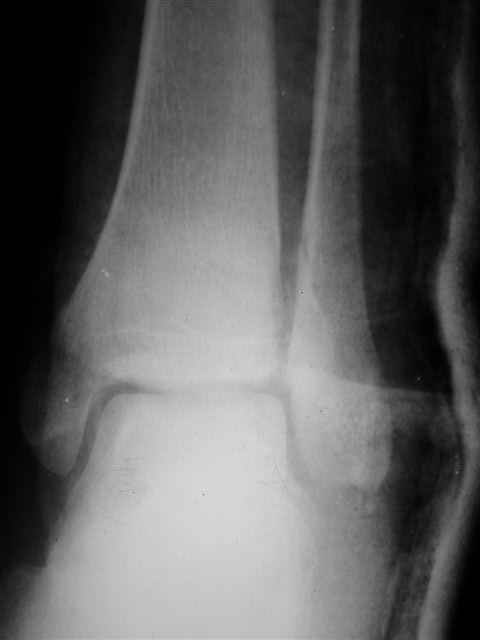

> интересуюсь тактикой лечения повреждений голеностопного сустава.

Ничего сверхъестественного, но если есть интерес, то в понедельник пересниму Рг-граммы и отправлю.

Уважаемый Иван,

Я предупреждал, что ничего сверхъестественного. Каюсь, что одна из спиц прошла несколько дальше, чем нужно было, но главное - перелом стабилизирован и больной работает суставом в полном объёме, несмотря на представленную раннее травму коленного сустава.